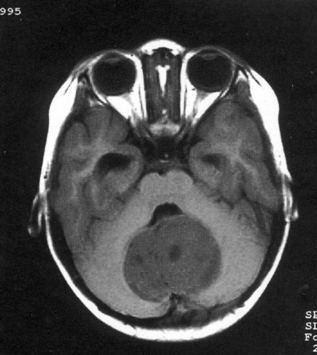

问题 病历摘要:??患儿男性,11岁。半年前开始出现行走不稳,常无故跌倒。半月前出现发作性剧烈头痛,伴恶心呕吐。体检:T36℃,P100次/分,R22次/分,BP100/60mmHg,神清,言语较缓慢,双眼外展约不及边,双眼侧视时有小幅度水平眼震。四肢肌力正常,右上肢肌张力较低,坐位姿势不稳,常不自主摇晃,双上肢指鼻不准,行走蹒跚步态,足距扩大,身前倾。 患儿目前出现了哪些方面的临床症状

选项 A.颅内压增高表现 B.小脑蚓部损害表现 C.动眼神经损害 D.滑车神经损害 E.展神经损害 F.面神经 G.锥体束征 H.锥体外系损害

答案 ABE